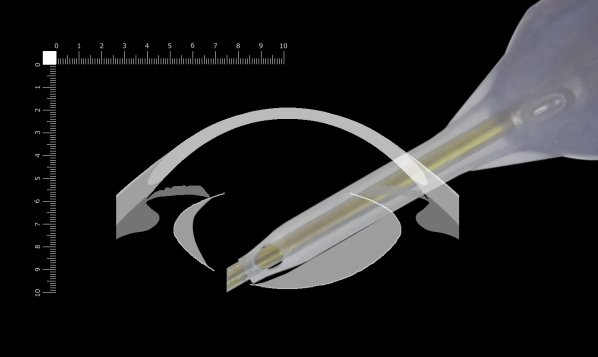

ここでは側面画像から考えます。

もう少し下方を考えます。ベベルは垂直なので掘っているところは辛うじて見えます。ここもまだ突き抜けて破嚢する危険があります。